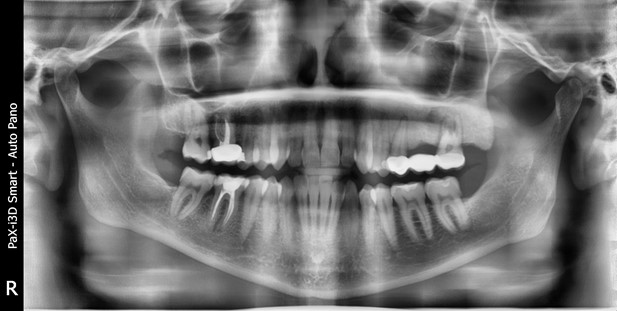

Вот вдогонку ещё случай у мальчика:

Внизу временный есть, а зачатка постоянного нет. Нет и зачатков седьмых зубов. Внизу нет пятых зубов, а наверху есть. В общем, тут хотя бы часть зубов прорежется нормально, но потом эти зубы будут двигаться, стараясь заполнить пустоту. К счастью, есть мы с имплантатами. У пациента всё будет хорошо.